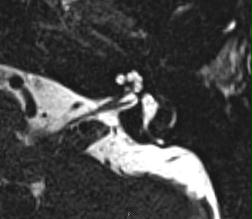

"Radiologie de l'Oreille - Technique d'imagerie et pathologie"

Samedi 3 mai 2014 - 8h-13h15

Auditoire Jéquier Doge, PMU, CHUV, Lausanne

Dr Patric HAGMANN

- Programme (pdf)